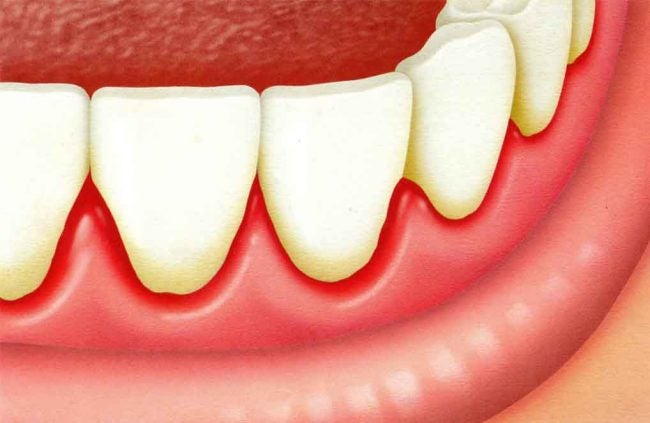

O que é boca seca? A boca seca é uma condição onde ocorre a baixa produção de saliva pelas glândulas salivares. Também chamada de xerostomia, pode ser causada por uma série de razões e deve ser tratada rapidamente. A saliva é muito importante para diversas funções da boca. Ela protege contra doenças e auxilia na…